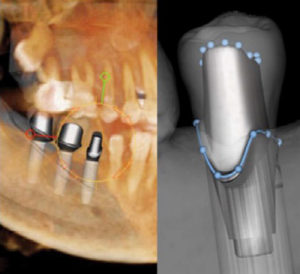

The data from CBCT scans led to a level of surgical predictability that I could not achieve with 2D imaging alone. Scans showed the buccal aspect of the teeth would have protruded too far into the cheek and the lip for the routine crown and bridge I had originally intended to pursue. With the i-CAT scan, surgical guides were created for placement of the implants. I worked with the laboratory to create custom castings and implant framework that protruded more lingually for a better aesthetic and clinical outcome. I facilitated a removable appliance that functioned like much of the tissue he lost after the oral surgery.